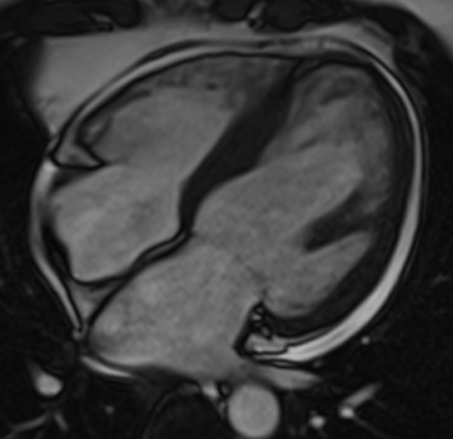

Cardiac magnetic resonance imaging (MRI)